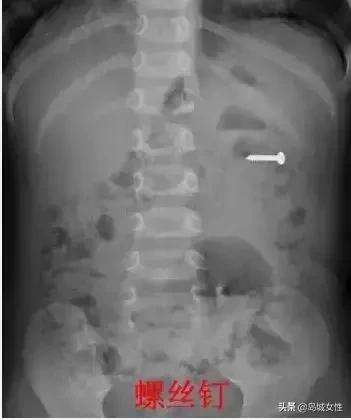

中秋假期第二天

青岛一个4岁孩子吞下

一根5厘米长的钢钉

当天傍晚6点20分

山大齐鲁医院(青岛)急诊科

接到一个即墨转院的孩子

值班医生刘超接诊后

直接心头一紧

当地医院拍的X线片显示

孩子肚子里有一根钢钉

已经5个多小时了

钢钉一端非常尖锐

随时会刺穿消化道

甚至腹腔内的大血管

刘医生赶紧带着孩子

做了X线片和CT

钢钉还在孩子的胃里

胃壁没有穿孔

接到通知的儿外科张蕾主任

也迅速赶到医院

第一时间通知手术室

和麻醉科进行胃镜检查

当晚7点40分

孩子被推进了手术室

可胃镜下的一幕

又让医生们吃了一惊

明明CT显示钢钉在胃里

可胃里空无一物

医生们继续向下寻找

终于在十二指肠球部

和降部交界的地方

发现了卡住的钢钉

钢钉的尖端已刺入

十二指肠球部的粘膜

后面就是大血管

再过一会儿

钉子可能穿出肠子

医生借助小儿胃肠镜设备

20分钟后钢钉被顺利取出

第二天复查,没有肠壁穿孔

孩子开始进食

现已顺利出院